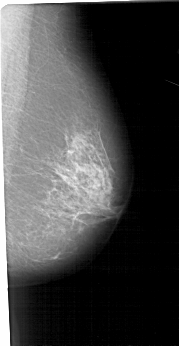

A_1706_1.LEFT_CC

LEFT_CC LINES 5326 PIXELS_PER_LINE 2416 BITS_PER_PIXEL 12 RESOLUTION 43.5 OVERLAY